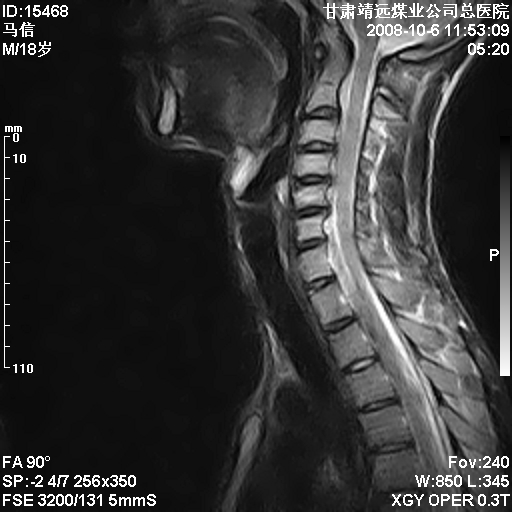

标题: MRI1827:颈椎内异常信号,是不是占位。

患者18岁,学生,在玩耍中受伤来检查,患者喜欢打篮球。颈椎内异常信号影,我们考虑占位,但是不像占位,又考虑硬膜囊的增厚,大家关建看颈椎椎管内的那个异常占位信号

颈椎建议做增强扫描;腰椎诸椎终板骨骺炎。

脑脊液流动伪影?

是正常的脑脊液波动伪影

脑脊液流动伪影

你说的占位是伪影。在我们医院1.5t和3.0t的mr上是经常看见的。